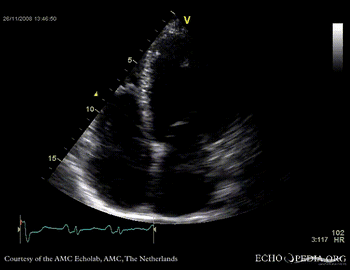

Dilated cardiomyopathy with severe mitral valve regurgitation

Courtesy of: J. Vleugels, AMC, The Netherlands